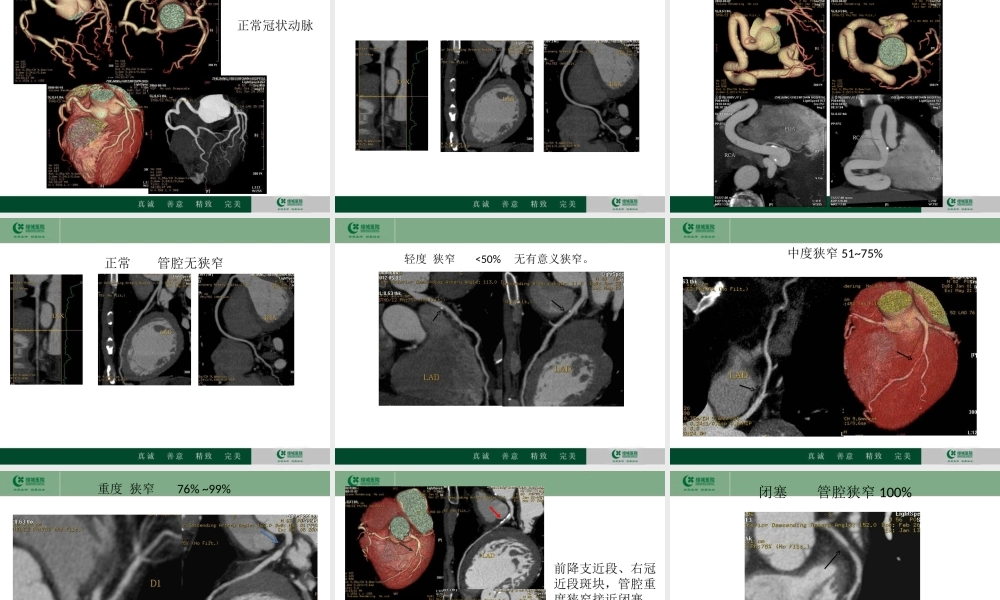

冠心病的CT检查价值放射科邱金海冠心病是严重危害人们健康的疾病,在许多国家,冠心病死亡人数居总死亡数的首位,而且,多数心血管病死亡发生在创造力最高、对社会和家庭贡献最大的年龄组。对此,有关专家呼吁,不吸烟、平衡膳食、经常运动和良好的心态,是保持心脏健康的四大要素。许多的名人如著名相声演员马季、侯耀文,著名小品演员高秀敏,还有最近中国共产党优秀党员、发改委副主任姚作汀等都是被冠心病夺去了生命。冠状动脉粥样硬化性心脏病是冠状动脉血管发生动脉粥样硬化病变而引起血管腔狭窄或阻塞,造成心肌缺血、缺氧或坏死而导致的心脏病,常常被称为“冠心病”。放射影像上诊断冠心病的标准是冠状动脉血管管腔狭窄超过50%。冠心病定义流行病学冠心病的患病率城市为1.59%,农村为0.48%,合计为0.77%,呈上升趋势。冠心病在美国和许多发达国家排在死亡原因的第一位。然而,美国从20世纪60年代开始,出现冠心病死亡率下降趋势。得益于60-80年代美国所进行的降低冠心病危险因素的努力,主要是控制危险因素和改进心肌梗死的治疗。2009年中国城市居民冠心病死亡粗率为94.96/10万,农村为71.27/10万,城市高于农村,男性高于女性。危险因素与诱因冠心病的危险因素包括可改变的危险因素和不可改变的危险因素。了解并干预危险因素有助于冠心病的防治。可改变的危险因素有:高血压,血脂异常(总胆固醇过高或低密度脂蛋白胆固醇过高、甘油三酯过高、高密度脂蛋白胆固醇过低)、超重/肥胖、高血糖/糖尿病,不良生活方式包括吸烟、不合理膳食(高脂肪、高胆固醇、高热量等)、缺少体力活动、过量饮酒,以及社会心理因素。不可改变的危险因素有:性别、年龄、家族史。此外,与感染有关,如巨细胞病毒、肺炎衣原体、幽门螺杆菌等。冠心病的发作常常与季节变化、情绪激动、体力活动增加、饱食、大量吸烟和饮酒等有关。症状•胸痛(心绞痛)•胸闷•心悸•呼吸困难•冠心病的主要临床表现有三种:心绞痛、心肌梗死和心性猝死。冠心病猝死的病理过程是,在冠状动脉硬化和心肌缺血的基础上,突然发生心脏骤停。猝死发生时如有旁人在场,应抓紧时间及时实施心肺复苏等抢救措施。如何来预防冠心病?检查方法•心电图•心电图负荷试验•动态心电图•核素心肌显像•超声心动图•血液学检查•冠状动脉CT•冠状动脉造影及血管内成像技术为什么要做CT,CT能解决什么问题?简介CT心脏冠状动脉成像在冠状动脉斑块的研究、冠心病、急性冠脉综合症及其它冠状动脉病变...